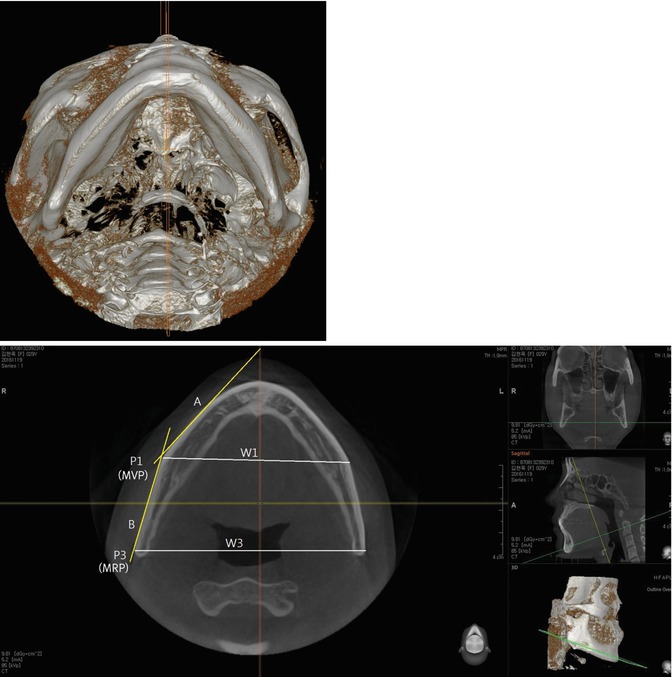

Fig. 7.4

The mandible of staight or outcurved type. (Upper) Three-dimensional submento-vertex view of the mandible. (Lower) Axial view. The gonial area is the most protruded area, and the bigonial distance is the widest (W3)

Regarding the mandibular body when viewed on computed tomography, the widest point is the intersection of the surface line of the mandibular body (A) and ramus (B) (Figs. 7.3, 7.4 and 7.5). This point (P1) is usually the thickest area, the average thickness of which is 17.8 mm, while that at the posterior angle area was 6.4 mm. This point is named as the maximum body point (MBP).

Three lines, two points, and three widths are used to describe the shape of the mandible on computed tomography (Figs. 7.4, 7.5 and 7.6). The line on the mandibular body surface is the body surface line (A), and the one on the ramus surface is the ramus surface line (B). In incurved type of the mandible, there is the third line in the posterior ramus, named as posterior ramus surface line (C). The maximal body point is marked by the widest and usually the thickest point on computed tomography and the intersection of the body surface line and ramus surface line (P1). The maximal ramus point is described as the intersection of the ramus surface line and posterior ramus surface line in the submento-vertex view (P2).